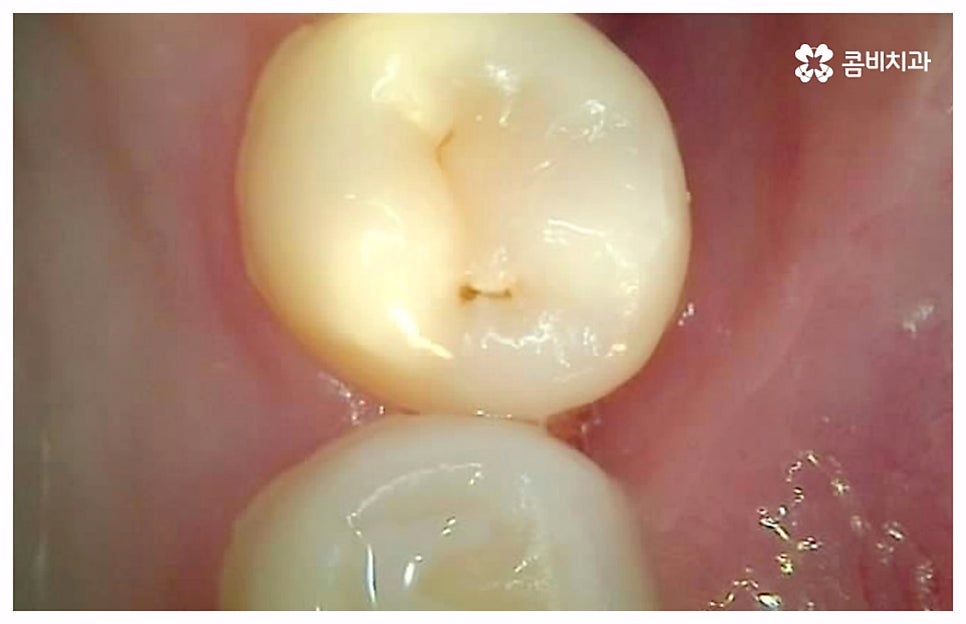

출처 아카이브 열기치통의 원인은 굉장히 다양한데 그 중 가장 대표적인 것으로는 구강 질환과 치아파절을 생각해 볼 수 있을 거예요. 충치나 잇몸병과 같이 구강 내부 상황으로 인해 발생하는 것이 구강 질환이라면 외부에서 충격을 받아 치아가 부러지거나 깨지는 것을 치아파절 이라고 할 수 있는데요. 이렇게 내적 또는 외적인 원인으로 생긴 치아 손상은 자연적으로 낫지 않으며 시간이 지날수록 빠르게 악화되기 때문에 구강 질환이 발생했거나 치아가 파절되었을 때 시기를 늦추지 말고 바로 치과에 내원하셔서 꼼꼼하게 검진을 받고 상황에 적합한 치료를 받으실 필요가 있습니다.

충치나 잇몸 질환은 보통 단계적으로 서서히 발전하기 때문에 환자분들께서 하루 아침에 극심한 통증을 느끼게 되는 경우는 많지 않지만 혹시라도 갑작스럽게 치통이 심할때 혹은 밤에 자려고 누웠는데 더욱 치통이 심할때 는 급성치수염을 의심해 볼 수 있어요. 급성치수염은 언급했던 충치나 외상성 치아 파절로 인해 치아 가장 안 쪽에 있는 치수 부분까지 세균이 침투하여 염증이 발생하는 것을 의미하는데, 이 때 감염된 혈관이 부어오르면서 단단한 치아 외벽에 둘러쌓인 치아 내부 압력이 올라가 작은 움직임에도 극심한 통증을 느끼게 되는 거예요.

급성치수염에 대한 치료는 보통 안쪽까지 침투한 세균을 깨끗하게 긁어내고 염증 및 괴사된 치수 부분을 삭제한 다음 뿌리관(근관)을 소독하고 치과 충전물로 밀봉하는 신경 치료를 통해 이루어지는데, 이렇게 신경 치료를 진행하고 나서 후속 치료로서 남아있는 자연 치아를 보호하고 저작 기능을 제대로 수행할 수 있도록 하기 위해 주변 치아와 크기, 높이 등을 맞추어 딱 맞게 제작한 보철물을 덮어씌우는 크라운 치료를 해 주는 것이 자연 치아를 보다 오랜기간 동안 건강하게 사용할 수 있도록 하는데 크게 도움이 된다고 할 수 있어요. 경우에 따라서 앞니의 경우 신경관이 많지 않기 때문에 레진으로 치료를 마무리하는 경우도 있으니 참고해 주시면 좋을 것 같아요.

이 때 신경 치료가 끝나면 보통 통증이 사라지기 때문에 추후 시간적인 부분, 금전적인 이유 등 여러 가지 사정들로 인해서 크라운 치료가 필수적이지 않으면 신경 치료만 받고 끝마쳐도 되는지 문의를 주시는 분들이 있는데요. 크라운 치료를 해 준 치아의 경우 밀봉만 한 치아 보다 훨씬 수명이 길기 때문에 환자분들께서 크라운 치료의 필요성에 대해서 잘 인지하실 필요가 있어요. 이것은 신경 치료를 받은 치과 환자 4만 6000명을 분석한 미국 연구팀의 발표를 통해서도 알 수 있는데요. 이에 따르면 근관 속의 손상된 치수를 긁어내고 소독한 뒤 충전물로 밀봉한 치아의 경우 평균 생존 기간이 11.1년이었던 것에 반해서 추후 크라운까지 씌운 치아의 평균 수명은 약 20년으로 길어졌다고 하니 의료진과 충분히 상담하셔서 자신의 상황에 잘 맞는 보철물로 크라운 치료까지 끝마치시길 권유드리고 있습니다.